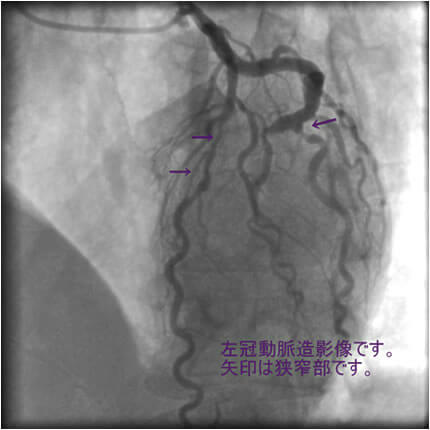

図1-3 左冠動脈造影像

よく解らないと思いますが、冠動脈に多数の狭窄があることと冠動脈が「こぶ状変化(医学用語で瘤状変化)」を生じているのが解ると思います。

「#1: 50% #2 :50% #3 #4PD #4AV:75% #5 50% #6 75% #7 75% #8 #9 #10 #11 #12 」

#1 、#2 などの数字は冠動脈の部位を表します。50%というのは正常の50%が狭窄しているという意味です。